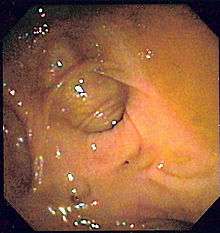

- Colonoscopy will show the diverticulum and rule out malignancy. A colonoscopy should be performed 4–6 weeks after an acute episode.